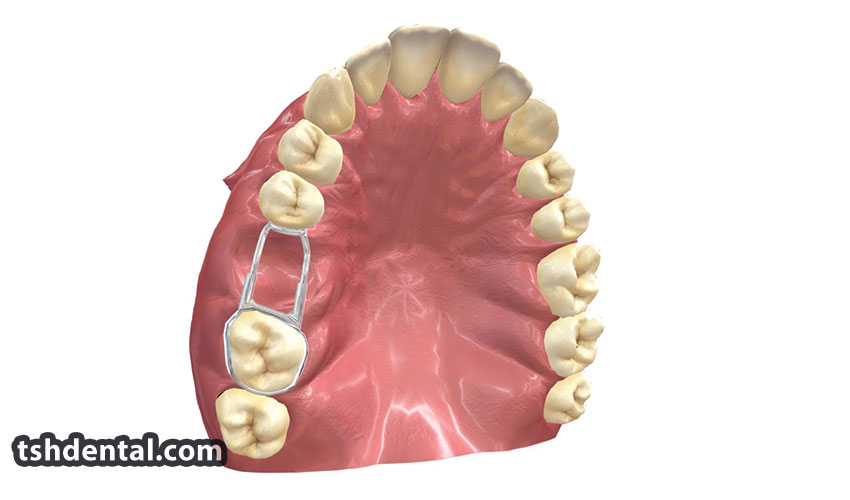

دیستال شو چیست؟

دیستال شو یکی از ابزارهای حیاتی در ارتودنسی است که برای حفظ فضای مناسب در فک و کنترل موقعیت دندانها استفاده میشود. این ابزار به متخصص...